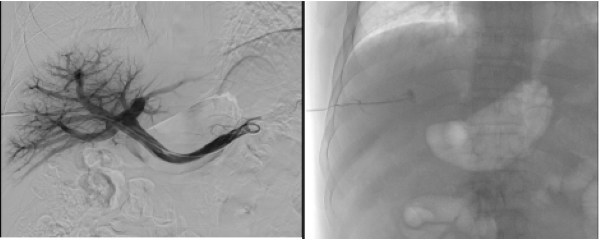

超声引导下肝门静脉穿刺

胰岛细胞经门静脉输注